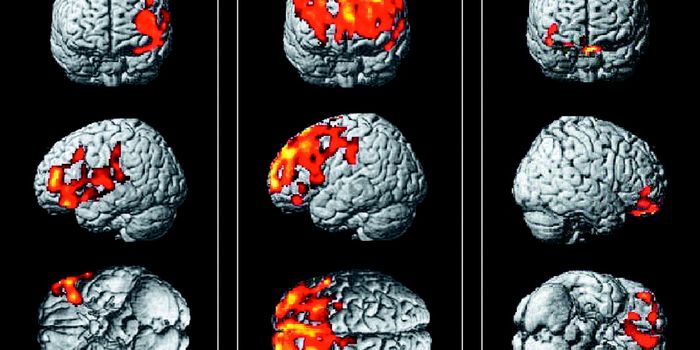

FEB 01, 2022Clinical & Molecular DXNeuroscientists have found a link between hotspots of brain overactivity and specific symptoms of schizophreni ...

MAY 16, 2017NeuroscienceWhen it comes to studying the brain, imaging is everything. The technology that allows brain tissue, neurons and network ...